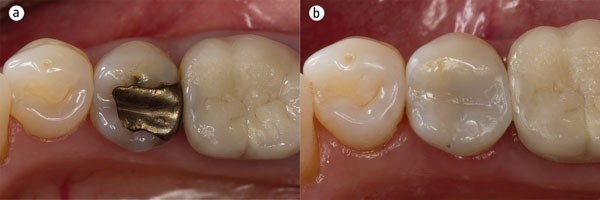

- جایگزینی پرکردگیهای قدیمی تیرهرنگ (مثل آمالگام) با مواد همرنگ دندان

این مواد نخست برای زیبایی دندانها در درمانهایی مانند کامپوزیت ونیر بهکار میرفتند، اما امروزه به دلیل مقاومت و چسبندگی بالا، برای ترمیم دندان های پوسیده، لبپریده یا شکسته نیز استفاده میشوند. مزیت بزرگ کامپوزیتها این است که برخلاف برخی مواد دیگر مانند آمالگام، نیاز به تراش زیاد دندان ندارند و به بافت دندان طبیعی آسیب کمتری وارد میکنند.